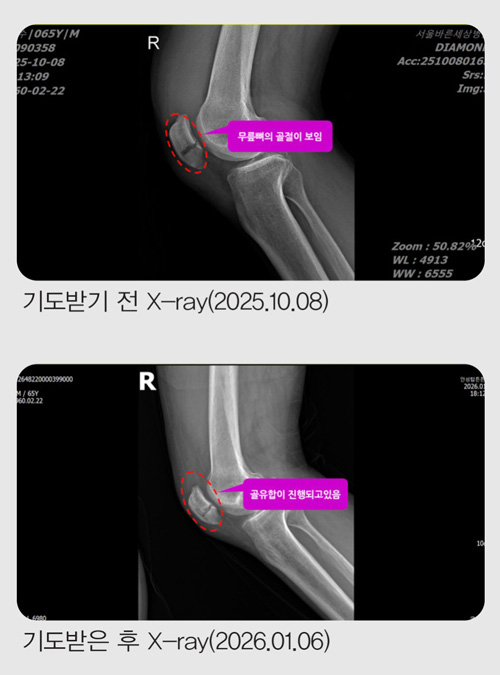

10¿ù 14ÀÏ, °ñÀýµÈ Áö 6ÀÏ ¸¸¿¡ Á¤Çü¿Ü°ú¸¦ ã¾Æ X-ray¸¦ Âï¾ú½À´Ï´Ù.

ÀÇ»ç´Â “»À°¡ °ÅÀÇ ´Ù Àß ºÙ¾ú½À´Ï´Ù. ÀÌÁ¦ °ü¸®¸¸ ÀßÇÏ½Ã¸é µË´Ï´Ù”¶ó°í ¸»Çß½À´Ï´Ù.

ÀÏ¹Ý »Àº¸´Ù Ä¡·á°¡ ±î´Ù·Î¿î ¹«¸»À°¡ ºÒ°ú ¸çÄ¥ ¸¸¿¡ ºÙÀº °ÍÀÔ´Ï´Ù. ÇÒ·¼·ç¾ß!